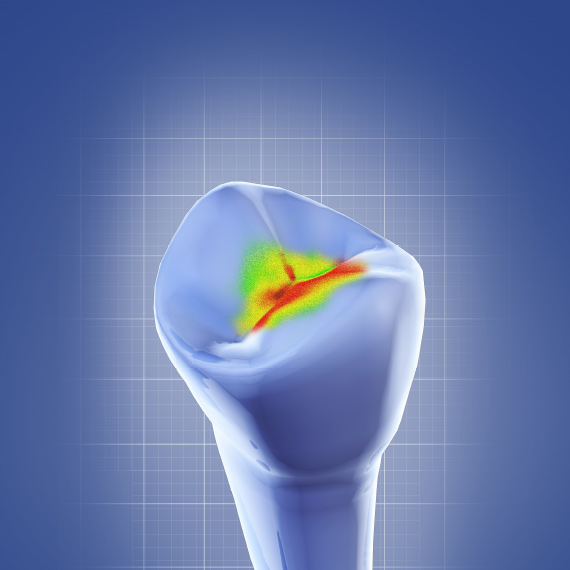

Early Diagnosis and Treatment of Asymptomatic Vertical Enamel and Dentin Cracks

Samer S. Alassaad, DDS

Wednesday, November 23, 2022

This Compendium eBook offers a continuing education (CE) article that presents a systematic approach for the early diagnosis and treatment of asymptomatic vertical enamel and dentin cracks based on current evidence. Download to earn 2 FREE CEU now!